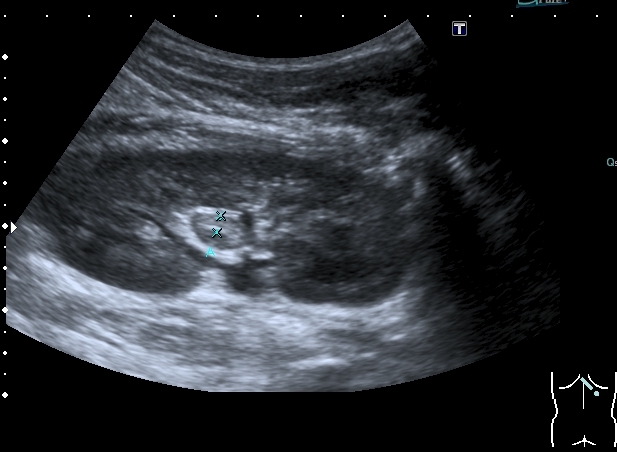

Левая почка

Она же

Поперечный скан

Как трактовать данные изменения - Пиелит? Гемапиелос? Отёк стенки лоханки ( по аналогии с желчным пузырём)?

Поэтому правильнее отталкиваться от того что мы видим. А видим мы классические признаки, которые встречаем чаще всего при воспалении ЧЛС - признаки пиелита - признаки отека стенок ЧЛС на фоне воспаления. Здесь аналогичная картина, но, вероятнее всего, вызванная травмой - надрыв - разрыв -нарушение целостности стенки ЧЛС - отек - асептическое воспаление.

Повреждение паренхимы в данной ситуации присутствует (контузия как минимум), но может быть и разрыв, направленый не наружу, а в сторону ЧЛС.